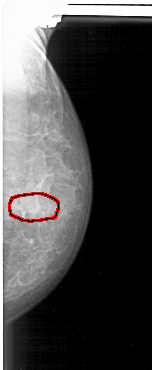

D_4165_1.LEFT_MLO

LEFT_MLO LINES 5041 PIXELS_PER_LINE 2326 BITS_PER_PIXEL 12 RESOLUTION 43.5 OVERLAY

FILE: D_4165_1.LEFT_MLO.OVERLAY

TOTAL_ABNORMALITIES 1

ABNORMALITY 1

LESION_TYPE CALCIFICATION TYPE ROUND_AND_REGULAR-PLEOMORPHIC DISTRIBUTION CLUSTERED

ASSESSMENT 0

SUBTLETY 3

PATHOLOGY BENIGN

TOTAL_OUTLINES 1

BOUNDARY